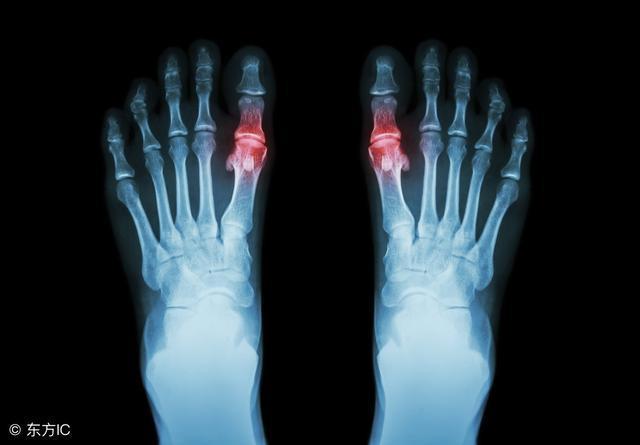

今年32岁的我,在五年前年纪轻轻的就患上了高尿酸血症,后来引发痛风。第一次痛风的时候脚趾大拇指关节红肿大,痛到想把脚截掉。一般正常尿酸值是200~450左右,我将近10天的青菜稀饭后,能正常走路去查尿酸时是680,我都不敢想象我痛风时的尿酸是多少,反正当时把我吓尿了。